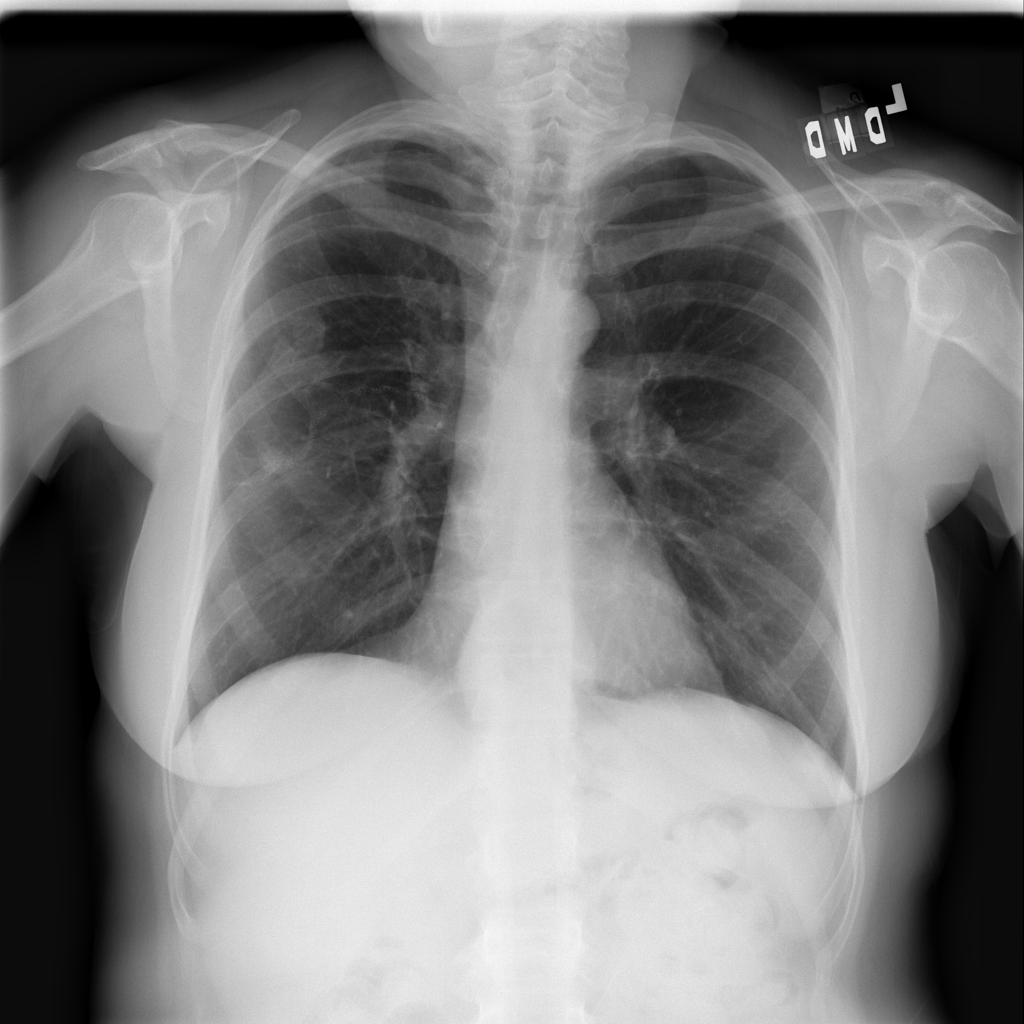

PAT-C048 · IMG-001Hernia

PAT-C048 · IMG-001

PA